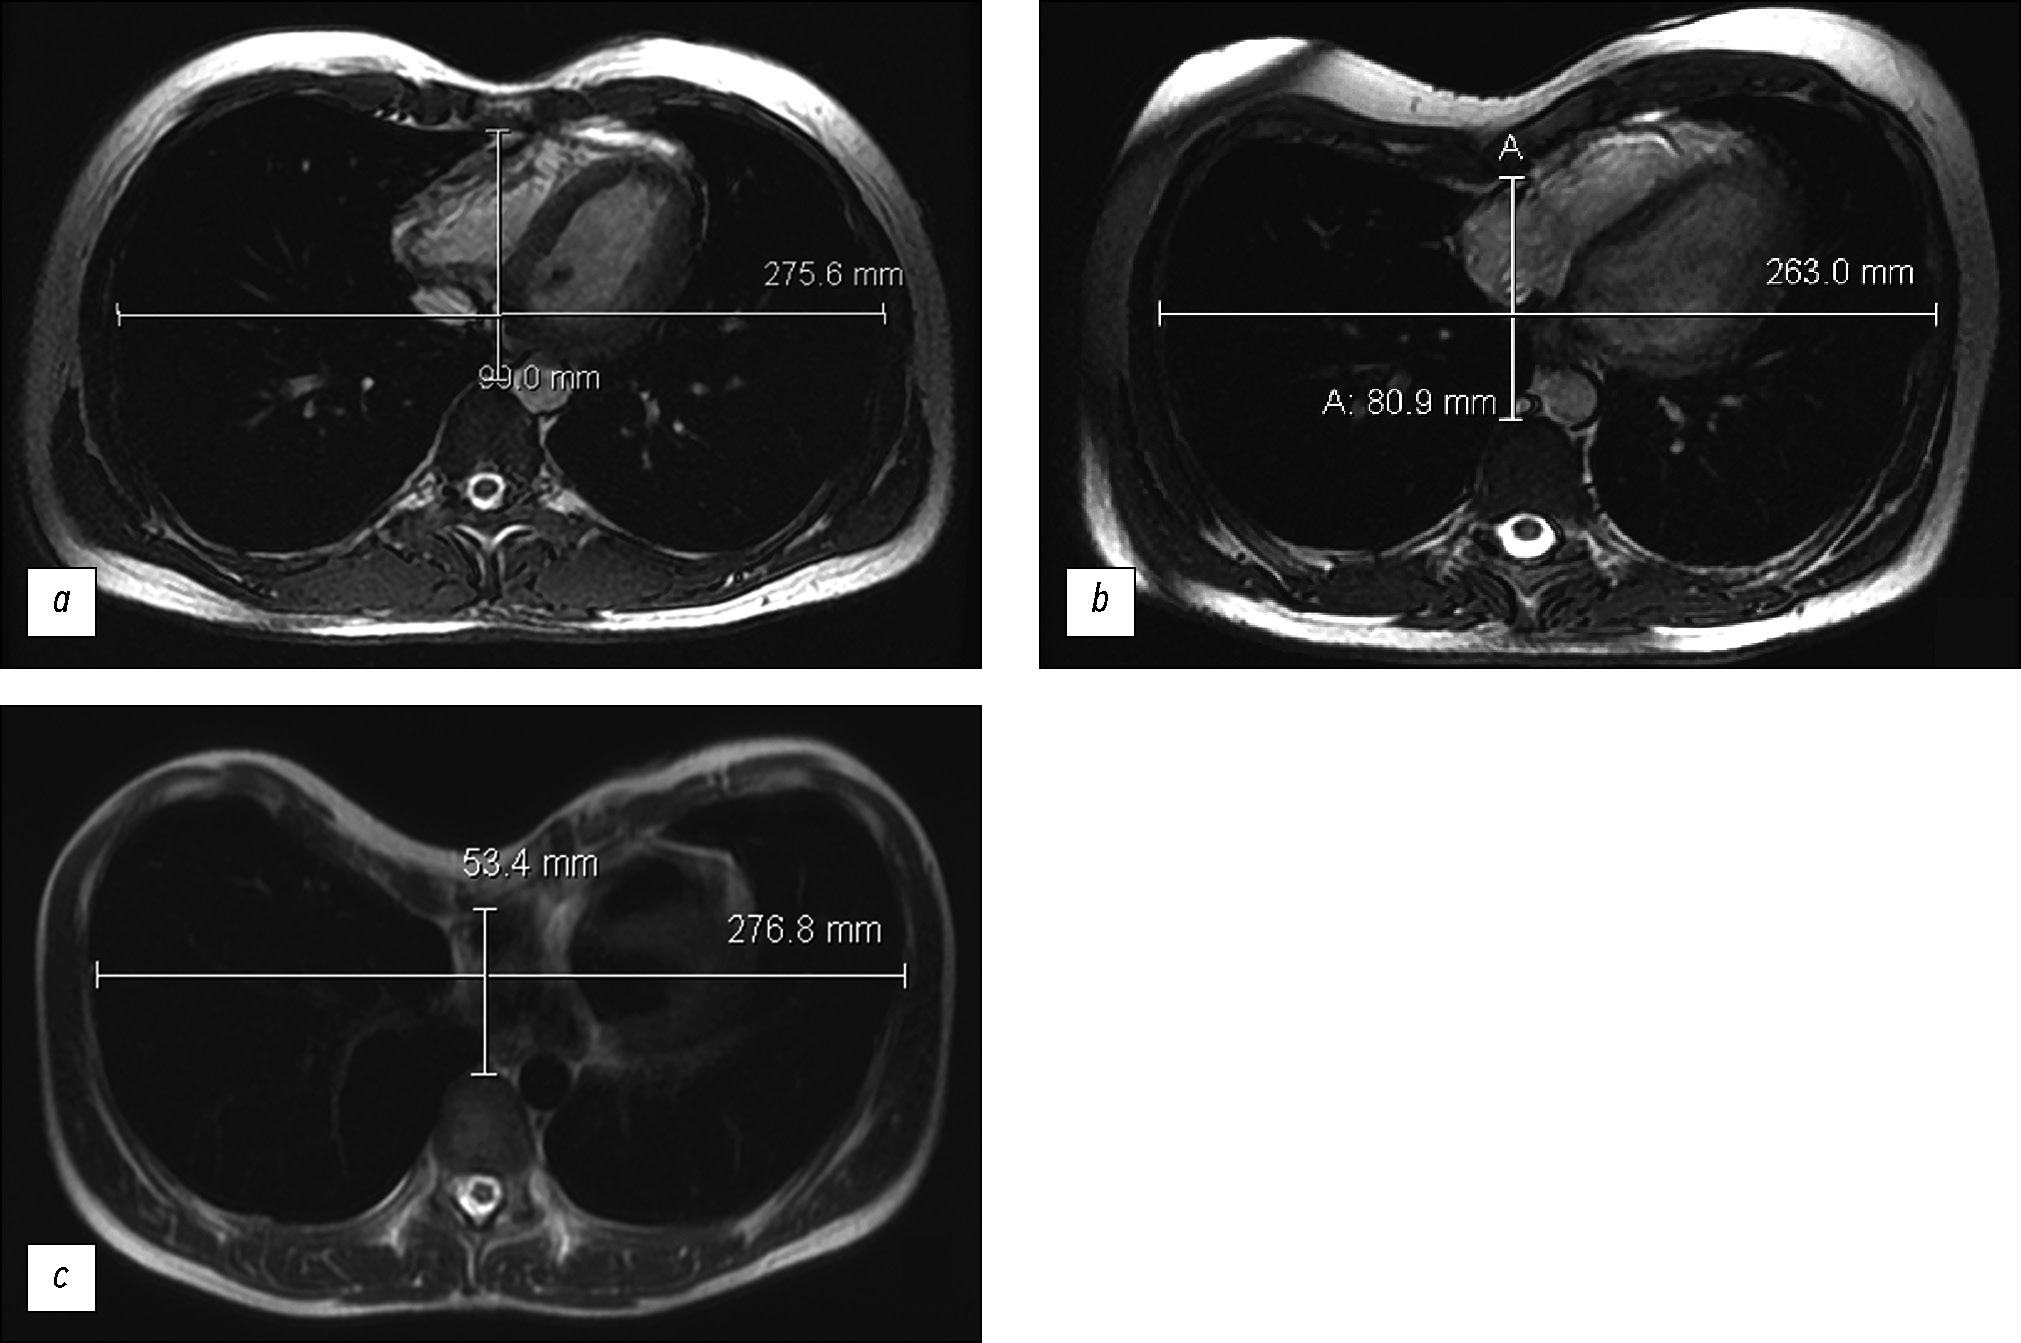

An angle of ≥150° was considered significant for surgery and was reported in 44.7% of the total number of patients (Table 3). This position of the sternum required a unique oblique positioning of the sternal plate. The plate was positioned “toward” the acute sternal angle in preparation for subsequent rotation. Consequently, the sternal plate was transferred from the upper intercostal space on the right to the lower intercostal space on the left by traversing the apex of the deformity with sternal rotation when the acute angle expanded to the right (Fig. 6a). This occurred in 86% of all sternal rotation cases. In the case of the acute angle expanded to the left (14% of all cases), the sternal plate was accessed from the lower intercostal space on the right, through the apex of the deformity to the higher intercostal space on the left (Fig. 6b).

Fig. 6. Frontal chest X-ray following pectus excavatum treatment. Plates positioned if the angle opens: (a) right; (b) left.